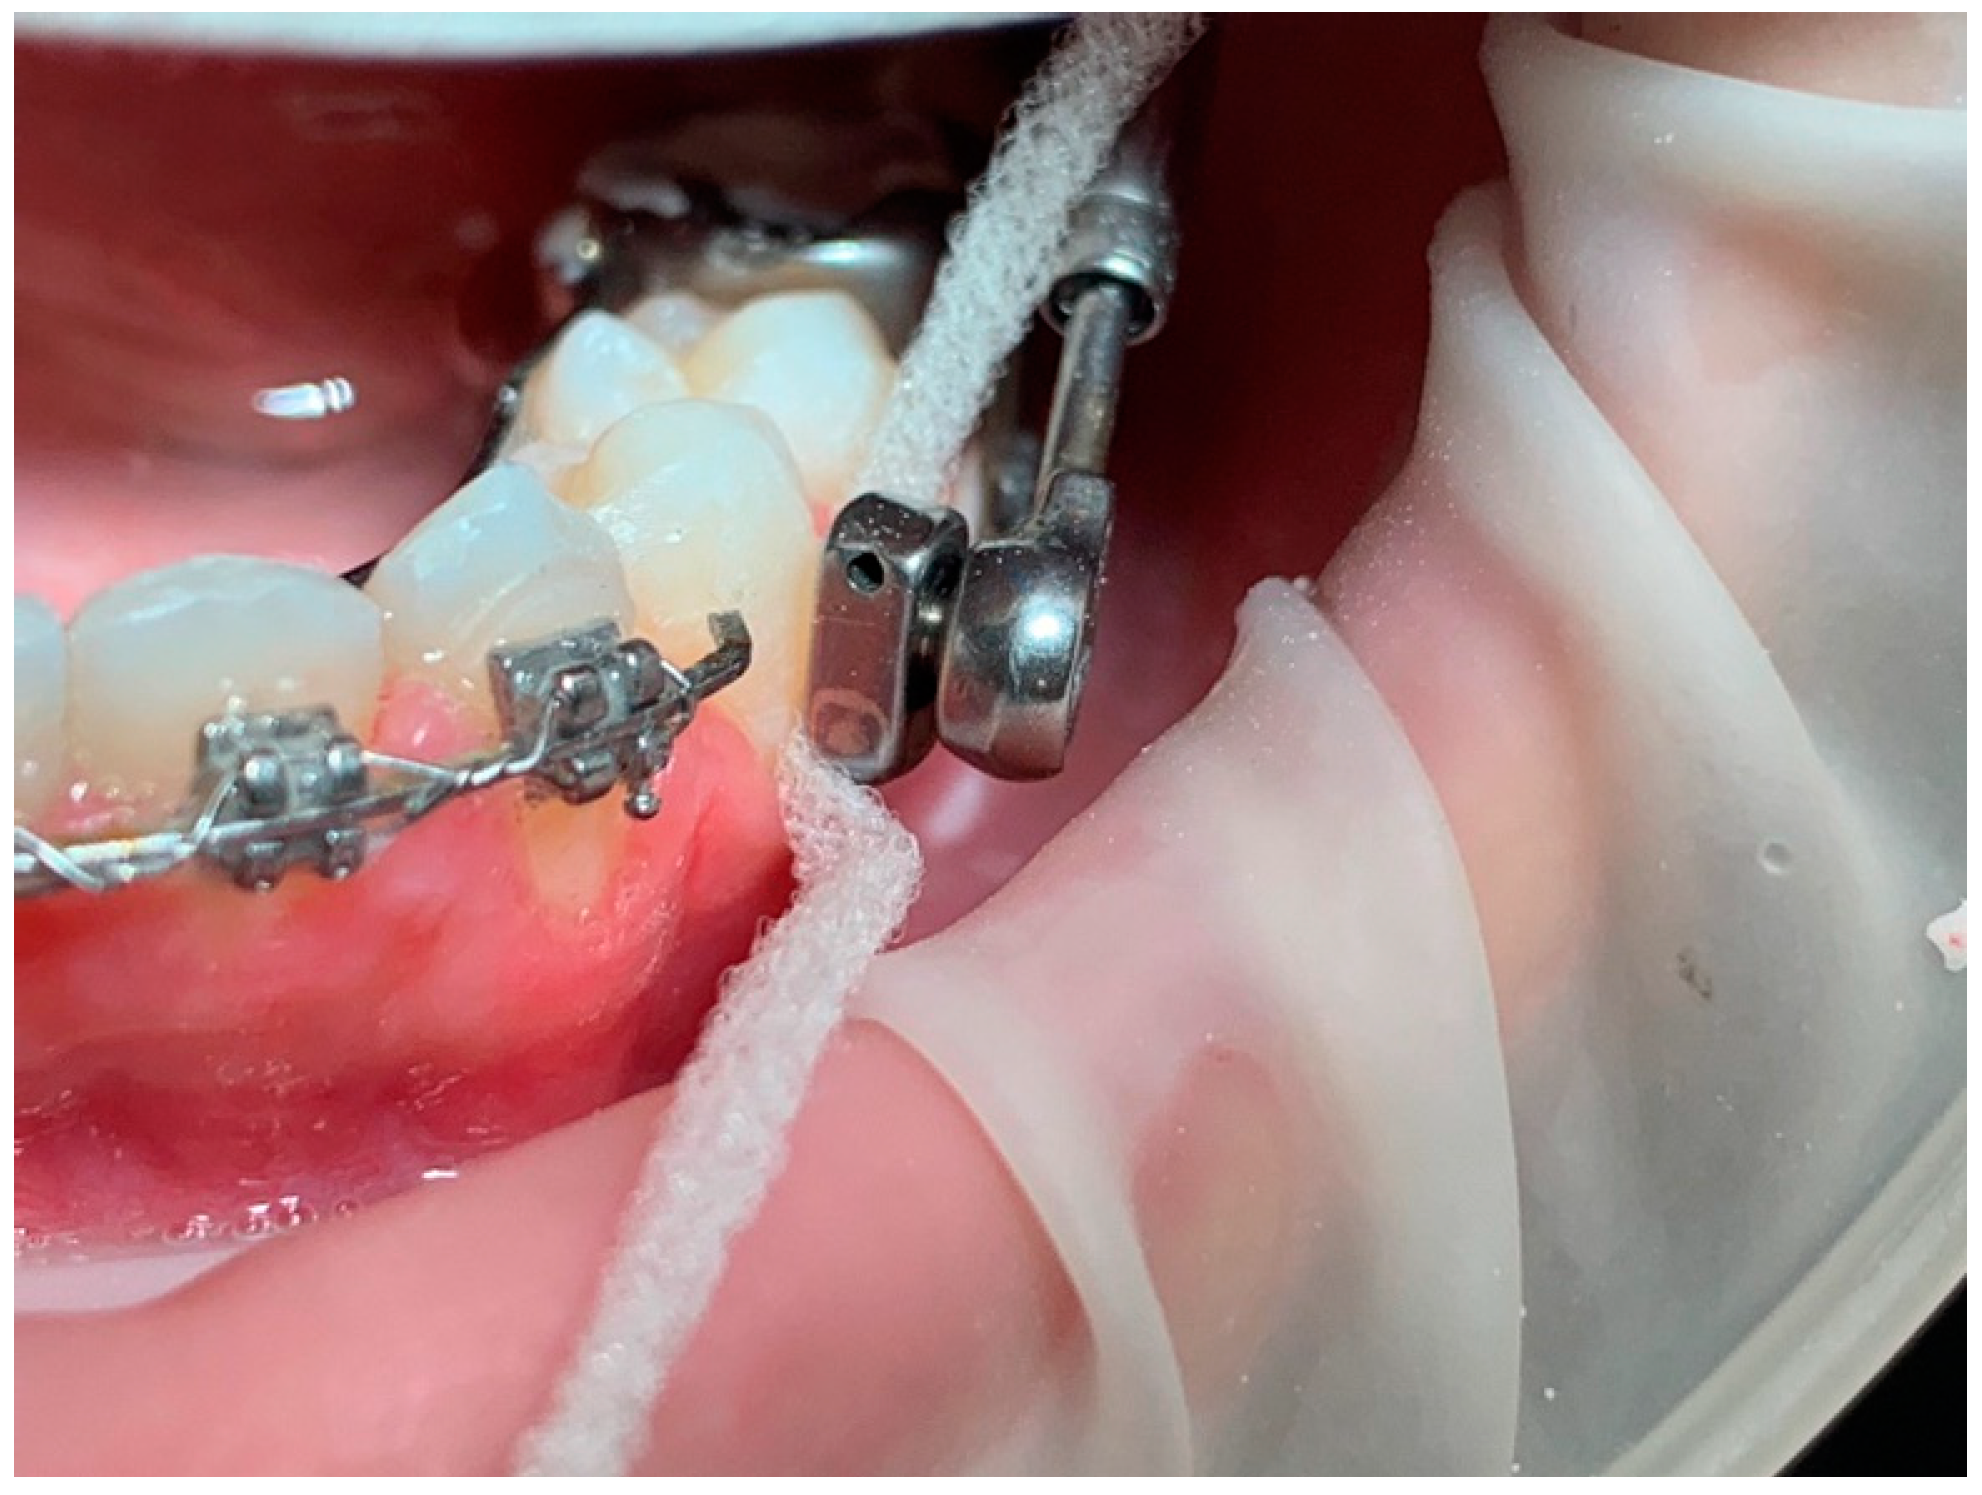

Figure 2a,b), coordination of the arches through coordinated final steel arches; coordination is checked clinically by manually guiding the patient and asking for the positioning of the protruding mandible with contact of the incisal edges with approximately 2 mm of overjet.

At this point of the treatment, the simplified Herbst device is applied: the dental arches remain spaced apart for a period of 7 days from the application of the device in the mouth. In this adaptation period, initially only the incisors of the upper arch make contact with those of the lower arch, in a ratio of 1mm of overjet (

Figure 3). The re-maining dental elements of the frontal group are supported by a rectangular sectional wire. Through the procedure of preparing the arches with MBA, phase with the Herbst device, and finalizing the therapy again with MBA, the treatment times in this clinical case were reduced in the phase with Herbst to 5 months compared to the 6-9 expected. This can be an interesting aspect both for less permanence of the device in the mouth which has a specific size, and for greater cleanability of the oral cavity and patient comfort.